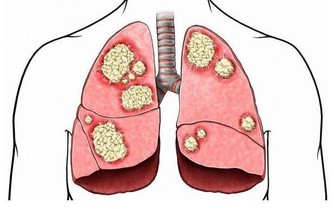

83.【肺癌】:半枝蓮30克,白石英30克。水煎服,每日一劑。